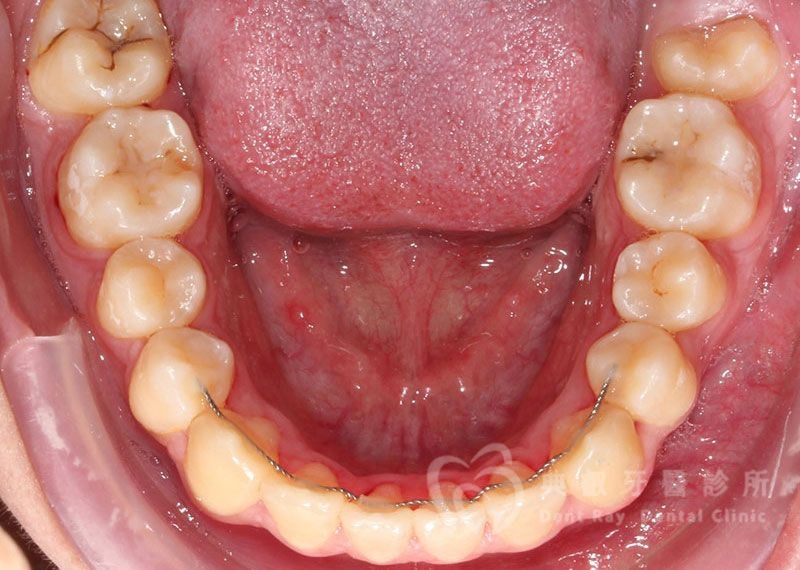

Before

After